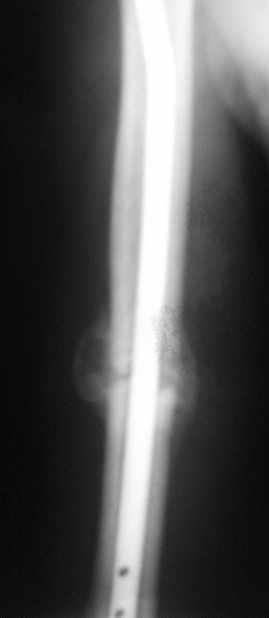

Блокируемый незаблокированный штифт.

Ортопедия и травматология Отправлено Andrey Sereda 29 Июнь 2008, 23:44

Уважаемые коллеги!Обратился пациент, оперирован не у нас.

Что делать?

Варианты:

1. Заблокировать.

2. Ничего не делать.

3. Заменить штифт на более толстый.

4. Еще варианты?

Спасибо. (Извините за снимки, дома нет негатоскопа, если необходимо - завтра пересниму).

однозначно не блокировать и не убирать - есть прекрасная мозоль и все отлично срастается. Мне плохо видно - выступает ли гвоздь проксимально ( кажется, нет, гвоздь строго в уровень с костью)?

Спасибо. А не слишком ли хороша мозоль?

Пациент обратился с жалобой на лигатурный свищ.

Амплитуда движений 70-80% от контрлаптеральной конечности с умеренной болью в месте перелома. Наиболее болезненно - заведение руки за спину (появляется боль в области плечевого сустава). Отведение - градусов 70, далее за счет лопатки.